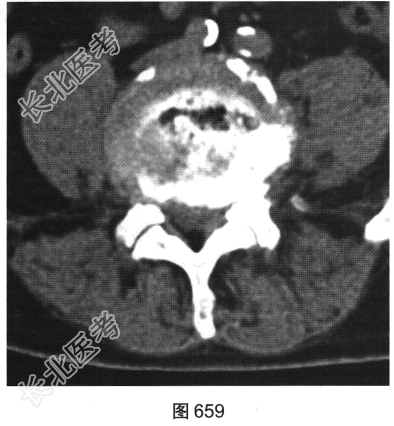

- 多项选择题2.[提示]患者行腰椎X线及CT检查,见图655~图659。患者有哪些阳性影像学表现( )

A、椎间盘“真空现象”

B、腰椎前滑脱

C、椎间盘膨出、突出

D、腰椎轻度侧弯

E、椎小关节骨质增生硬化

F、腰椎间隙变窄

- 多项选择题4.综合X线、CT和MRI图像,该患者有以下哪些腰椎退变征象( )

A、终板炎

B、腰椎间盘突出

C、许莫结节

D、黄韧带肥厚

E、腰椎管狭窄

F、腰椎间盘脱出,髓核游离